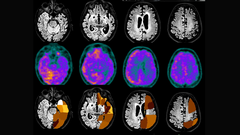

La especialista se muestra «escéptica» ante estas terapias y remarca la importancia de controlar los factores de riesgo, que podrían reducir en un 50 % las probabilidades de desarrollar la enfermedad

La experta remarca la importancia de la alimentación a la hora de prevenir enfermedades, ya que «las personas que siguen una dieta mediterránea reducen en un 53 % el riesgo de desarrollar alzhéimer»